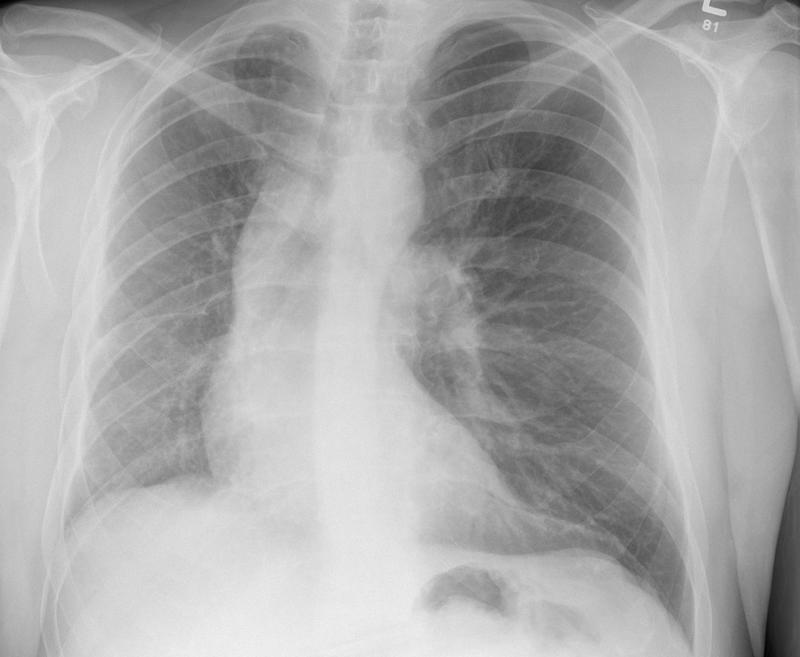

Gallery Congenital Hypoplastic Rt lung

Hypoplastic Rt lung